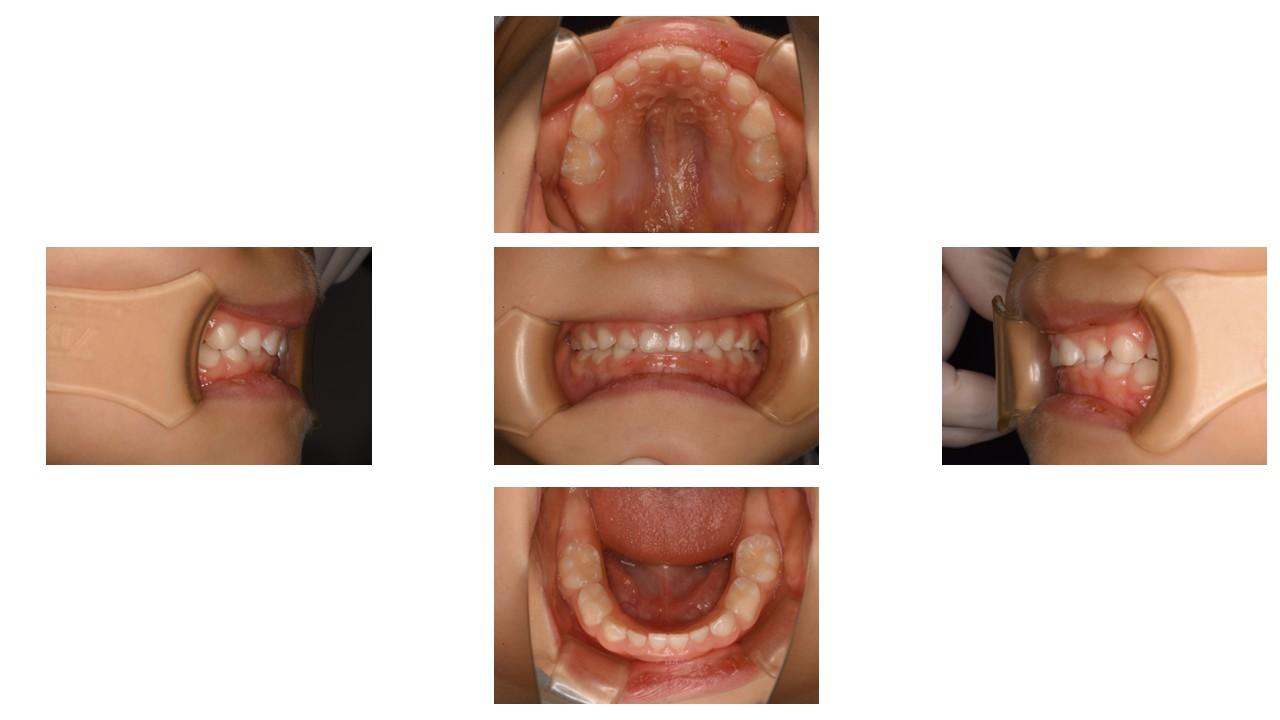

「叢生」は、一般的に「乱ぐい歯(らんぐいば)」「八重歯(やえば)」「ガタガタの歯並び」などと呼ばれる状態で、日本人に非常によく見られる不正咬合(ふせいこうごう:良くない噛み合わせ)です。

<叢生の状態>

顎(あご)の骨の大きさに対して、歯のサイズが大きすぎたり、歯が並ぶスペースが不足していたりするために、歯がデコボコに重なり合って生えている状態を指します。

【叢生を治す必要がある理由】

叢生は見た目の問題だけでなく、お口の中の健康を維持することを難しくし、将来的に様々なトラブルを引き起こす原因となります。